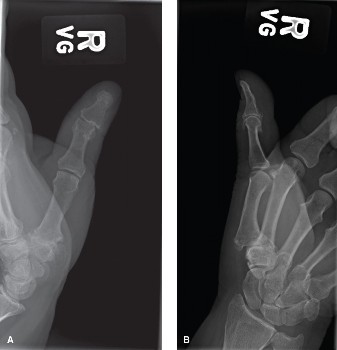

CASE 20 A 69-year-old female presents to office with pain in the right thumb fo…